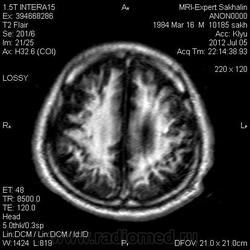

1 случай -локальная гемиатрофия.2 случай-диффузная.

Молодой человек после автомобильной аварии.3 года лежит.Двигаются только глаза.Зрелище душещипательное.

Евгений, конечно же, мои случаи не являются "чистой" атрофией-согласна.Мне пока не встречались случаи болезни Пика, Альцгеймера и другие "чистой воды" атрофии.Второй случай- состояние после длительной комы вследствие автодорожной травмы 3 года назад.Пациент проходил исследование в прошлом году , в этом родители привезли на динамику.